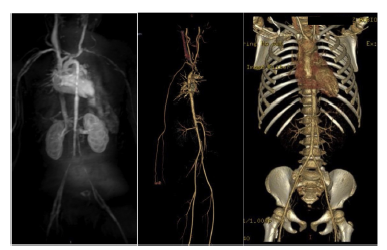

After 10 months (2016), the patient was without control treatment. A magnetic resonance angiography reported segmental stenosis, moderate post-stenotic dilation, and areas of caliber reduction in the infrarenal abdominal portion, important stenosis in the origin of the left iliac, and abnormality of segmental caliber in supra-aortic trunks; hence, treatment was started with methotrexate, folic acid, and immunoglobulin (Fig. 2).

Fig. 2 Compilation of control imaging studies. From left to right: magnetic resonance angiography (2016) with evidence of multiple strictures; CT angiography (2017) without abnormalities; CT angiography (2019) with the absence of anomalies.